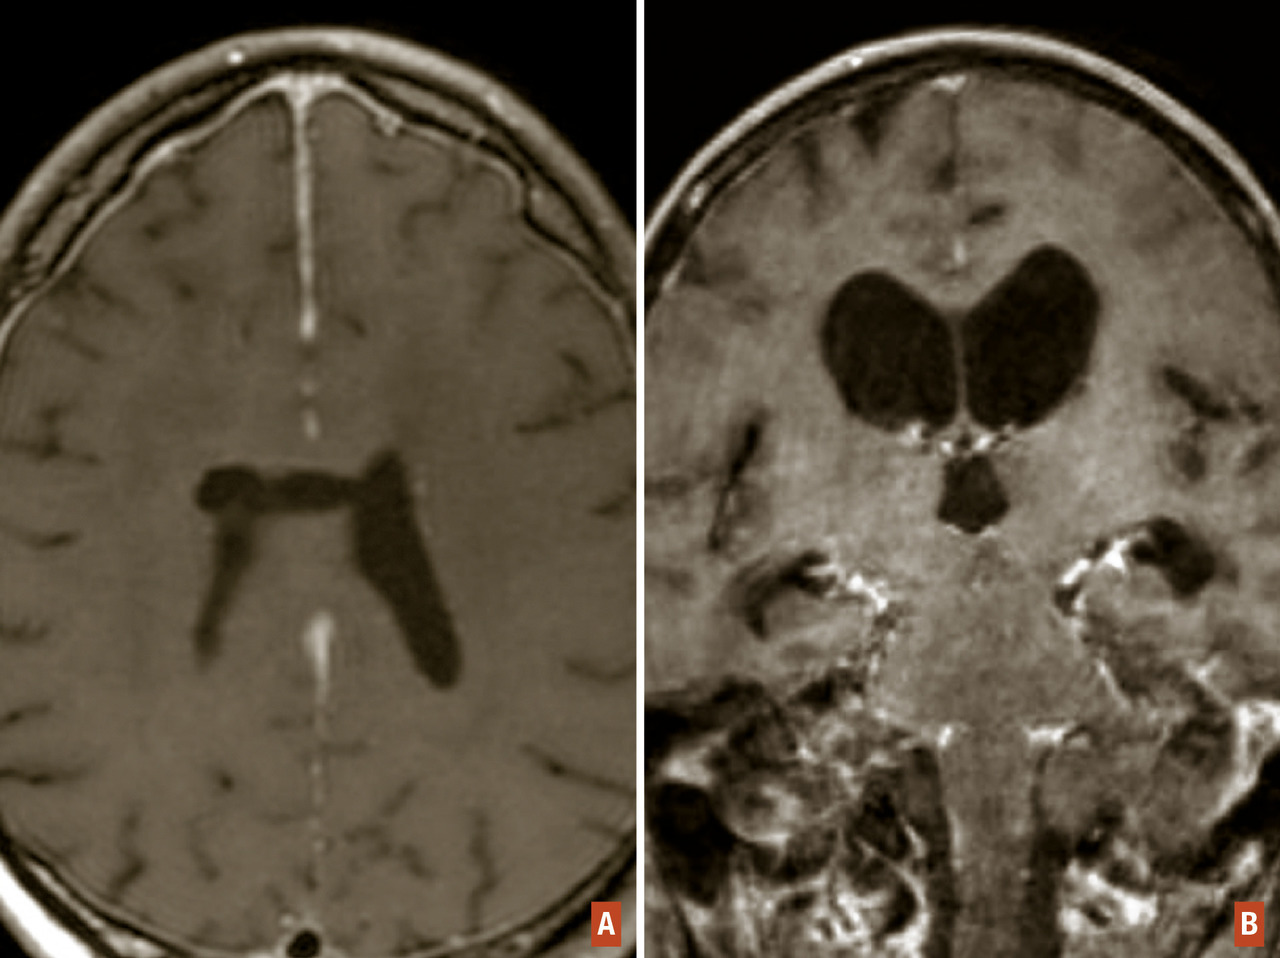

La suspicion d’une tumeur cérébrale doit conduire à une imagerie cérébrale. Le scanner cérébral sans et avec injection de produit de contraste est habituellement réservé en cas de contre-indication à l’imagerie par résonance magnétique (IRM) ou dans certaines situations d’urgence où une IRM ne peut être obtenue rapidement. L’IRM cérébrale représente actuellement l’examen de référence. Elle a plusieurs rôles : localiser le processus, préciser ses caractéristiques, diagnostiquer de possibles compli­cations (engagement, hémorragie, hydrocéphalie…), contribuer à définir la suite de la stratégie diagnostique et thérapeutique. Elle doit être réalisée optimalement dans les trois plans de l’espace et comporter une séquence T1 sans et avec gadolinium, une séquence T2 et/ou FLAIR. L’IRM multimodale (fig. 3) permet d’obtenir des informations complémentaires sur les caractéristiques de la lésion. Ainsi, la spectroscopie IRM permet d’évaluer le degré de prolifération cellulaire d’une lésion (rapport choline/N-acétyl-aspartate augmenté dans les tumeurs agressives). L’IRM de perfusion, en analysant le volume sanguin cérébral relatif au sein de la lésion identifiée, permet de quantifier la présence d’une éventuelle néoangiogenèse tumorale caractérisant les gliomes malins.

Le diagnostic d’hypertension intracrânienne est clinique. Le signe clinique le plus fréquent est représenté par des céphalées. Leur séméiologie peut avoir un caractère assez variable : diffuses, en hémicrânie dans les tumeurs hémisphériques, ou de la région occipitale dans les tumeurs de la fosse postérieure. Parfois, elles peuvent revêtir un caractère pseudo-migraineux, et s’accompagner de vomissements classiquement « en jet ». La présence d’un œdème papillaire est inconstante, en particulier chez le sujet âgé. Il ne s’accompagne pas d’une baisse d’acuité visuelle, ce qui le différencie de celui accompagnant une papillite inflammatoire. Cependant, si la stase papillaire est importante et se prolonge, elle peut donner lieu à des épisodes d’éclipse visuelle pouvant précéder une cécité liée à une atrophie optique. On peut observer aussi une paralysie du VI se manifestant par une diplopie mais qui n’a pas de valeur localisatrice de la lésion. L’hypertension intracrânienne peut être révélatrice de la tumeur ou survenir dans l’évolution d’une tumeur cérébrale déjà connue. L’imagerie (scanner ou IRM cérébrale) permet d’en déterminer la ou les causes (développement tumoral, œdème péritumoral ou autres complications suscitées) et d’en évaluer l’importance par l’effet de masse exercé sur les structures anatomiques du cerveau et d’anticiper les conséquences menaçantes (fig. 6).